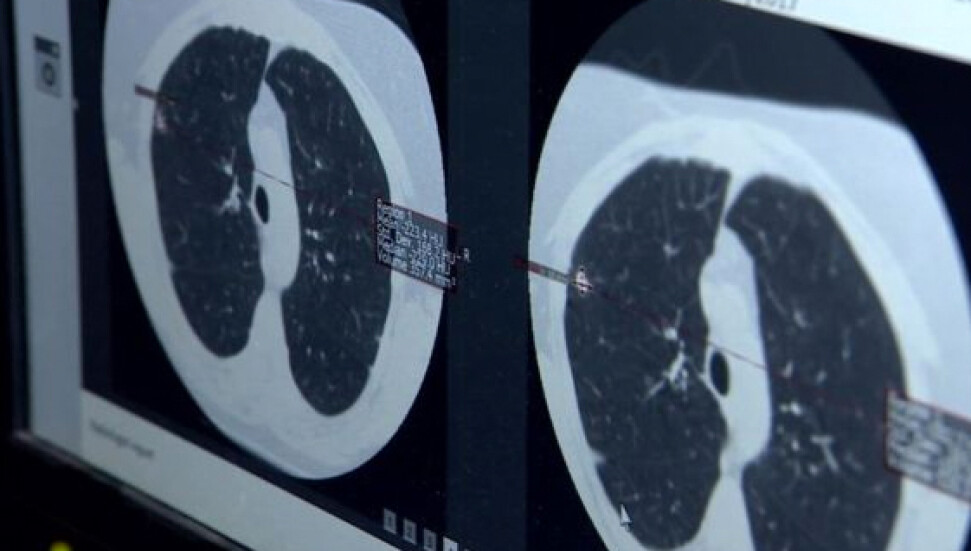

Turan, "Virüsün şiddeti devam ediyor. Yarattığı akciğer hasarı inanılmaz. Bir yoğun bakım hekimi olarak söyleyebilirim ki gördüğümüz akciğer filmleri ve tomografileri olayın şiddetinin oldukça fazla olduğunu ve bu hasta gruplarının da zannedildiği gibi çok ileri yaş olmadığını; yaşamı içerisinde aktif yaşamını devam ettiren bireylerin de çok ağır klinik tablolarla bize başvurduğunu söylemek zorundayım" dedi.

"Hastanın akciğer tomografileri ve filmlerini gördüğünüz zaman 'Bu hastalar acaba nasıl nefes alabiliyor?' diyebileceğiniz görüntüler. Bizim halkımızdan tek beklentimiz kurallara uysunlar ve yoğun bakıma ihtiyaç duyulmasın; yoğun bakım ortamı gerçekten zor bir ortam, hastalar için de çok sıkıntılı bir yer. Kendilerinin buna ihtiyaç duymamaları için kısıtlamalara uyulmasını tavsiye ediyorum."